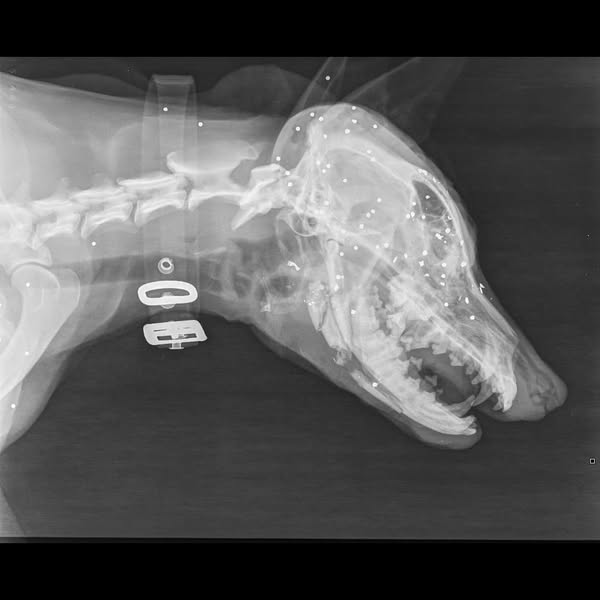

Ήταν πυροβολημένο στο πρόσωπο με καραμπίνα εξ επαφής, είχε σπάσει η γναθος, είχε πολλαπλές κρανιοεγκεφαλικες κακώσεις και η κατάστασή του ήταν ιδιαίτερα κρίσιμη.

Υπήρχε και δεύτερος πυροβολισμος στη σπονδυλικη στήλη.

Δόθηκαν οι πρώτες βοήθειες με την ελπίδα να σταθεροποιηθει, εστάλησαν ακτινογραφίες σε κτηνιάτρους, ώστε μετά να συζητηθούν τυχόν χειρουργικές επεμβάσεις που θα χρειαστούν.